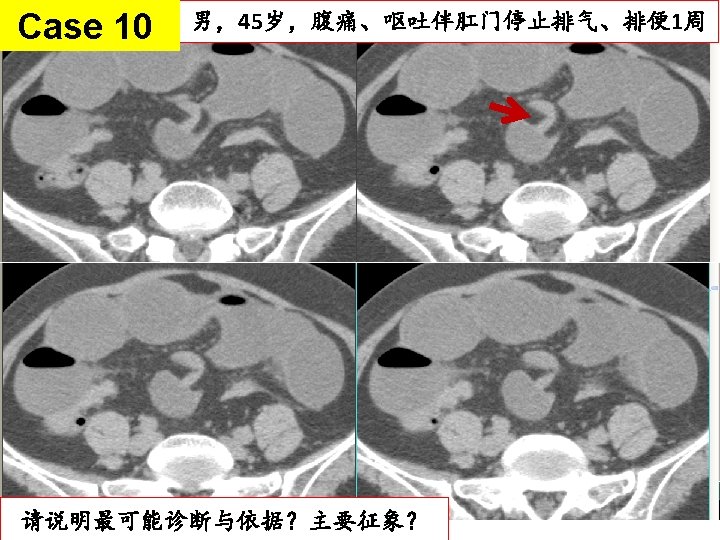

粘连性肠梗阻 fat notch sign